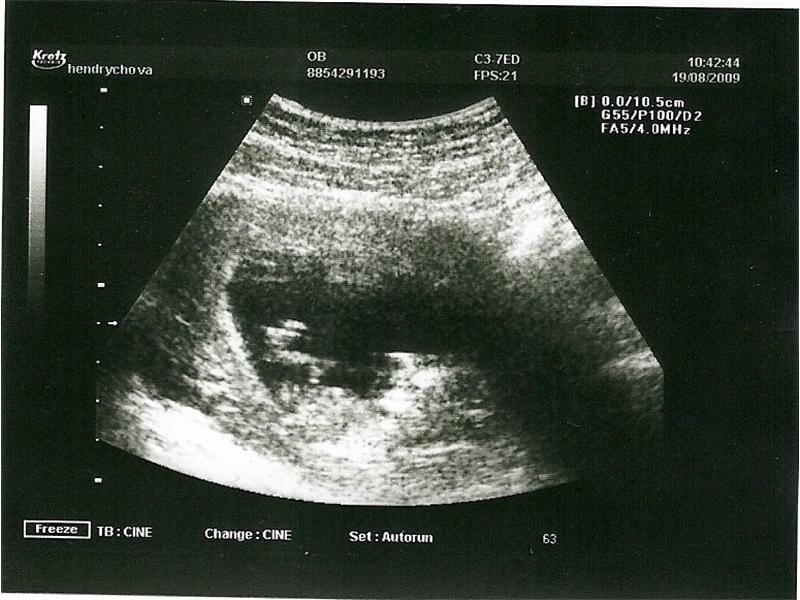

Zdroj: archiv redakce